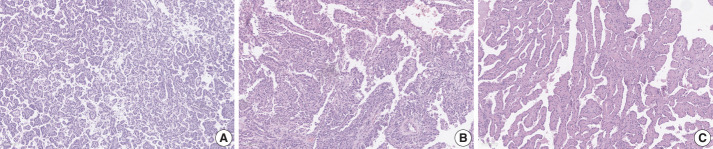

Abstract Image